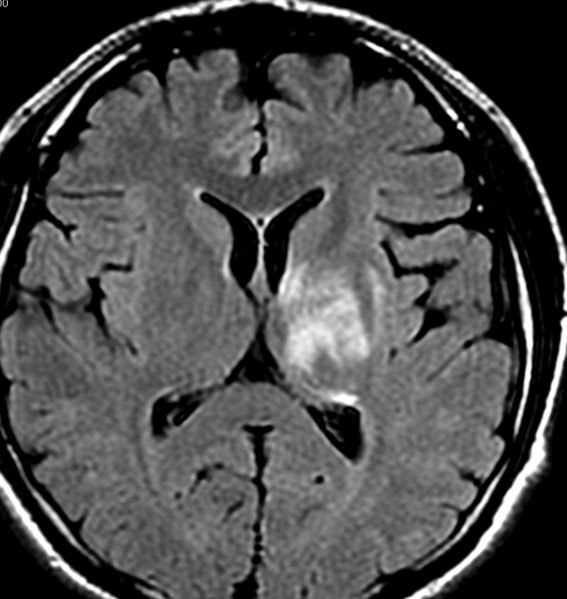

放射線治療13週目

右はガドリニウム増強です。ステロイドとグリセオールの点滴では制御できませんでした。悪性神経膠腫の病名で保険適応があるアバスチン(ベバシズマブ 10mg / kg)の投与を開始しました。

アバスチン投与後15日目

たった2週間で劇的な改善が見られました。失語症と片麻痺や認知機能も改善しました。